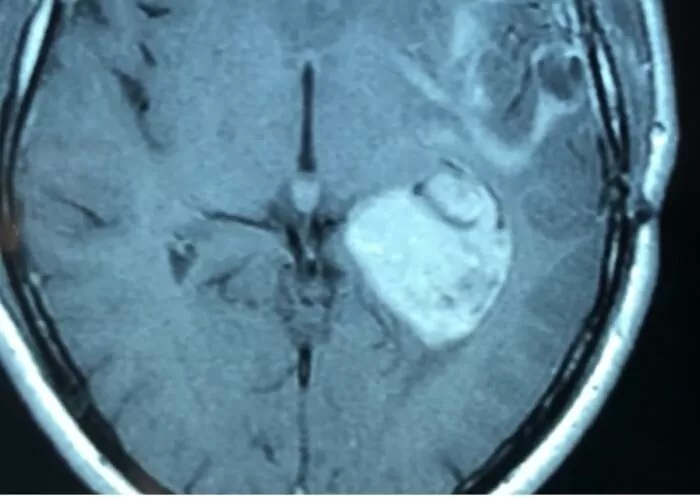

Менингиома - симптомы и лечение

Лечение астроцитомы

Диагностика опухолей головного мозга